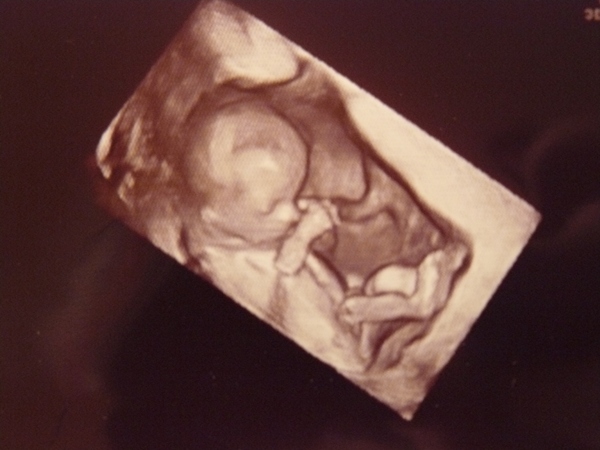

jobb híján..ugyanis az igazán hasonló evés alvás előtt van, van egy még jobb kép de most nem találom:(

jobb híján..ugyanis az igazán hasonló evés alvás előtt van, van egy még jobb kép de most nem találom:(

a keze az ála alatt azon könyököl

a keze az ála alatt azon könyököl

idekint 1 hetesen:)

idekint 1 hetesen:)